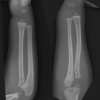

A 62-year-old man injured his right thigh by falling down from a height of around 10–12 feet on a wooden log. He developed pain and swelling over the right thigh within an hour for which he was taken to the local hospital. He was treated with injectable analgesics and discharged after few hours prescribing some oral analgesics and anti-inflammatory drugs. After reaching home, the severity of the pain gradually increased with associated numbness in the leg which was not responding to analgesic and anti-inflammatory drugs. On the next day, he visited the same hospital, the treating doctor again gave him parenteral analgesic, even then the pain did not subside and hence, they referred him to our hospital. The patient presented to us exactly 24 h after his injury. He complained of severe pain and swelling over the right thigh with loss of sensation and inability to move his affected limb which was gradually progressive and did not subside with any kind of analgesics or anti-inflammatory. In the course of the 24 h of the injury, the patient normally passed stool and urine. The patient had no significant history of illness. The patient had no history of any clotting disorder and neither of his family had suffered from any kind of bleeding diathesis. The patient neither had given any history of anti-coagulant use nor any significant drug intake. On examination, the patient was alert, conscious, and well oriented to time place and person. His blood pressure was recorded to be 148/90 mm of mercury and pulse rate of 100 per minute. On inspection, the affected thigh was grossly swollen and the overlying skin was shiny and the attitude of his hip and knee was mildly flexed. There was an ecchymosis of size around 10 × 6 cm2 over the anterolateral aspect of the thigh. On palpation, the thigh was severely tense and there was severe pain on attempted passive flexion and extension of the knee. There were no abnormal mobility and no bony crepitus in the affected limb, and the patient was able to do active straight leg raising. The affected limb was cold distal to the thigh compared to the opposite normal limb. There was lack of sensation below the knee and there was no motor activity distally. Distal pulse in the affected limb was feeble and distal SpO2 was fluctuating. Plain radiograph of the femur did not show any evidence of bony abnormality or fracture. USG color Doppler of the right lower limb showed gross collection in the anterior compartment of the thigh, subcutaneous edema, and decreased (monophasic) flow in the distal part of the femoral artery till the dorsalis pedis artery. Therefore, on the basis of the classical signs (six P’s, i.e., pain out of proportion, pain on passive stretch, pallor, paresthesia, pulselessness/ feeble distal pulse, and paralysis distal to the injury), a clinical diagnosis of compartment syndrome of the thigh involving the anterior compartment was made. Due to the late presentation, compartmental pressure measurement, further radiological investigations such as CT angiography, magnetic resonance imaging, and CT scan of the thigh were not done to avoid further delay in the definitive procedure, that is, the fasciotomy. The patient was prepared for emergency fasciotomy with emergency pre-operative work out within 3 h of presentation to the emergency department. The patient was placed in supine position on the operating table under spinal anesthesia. Under all aseptic and antiseptic measures, proper painting with 10% povidone-iodine and proper draping was done on the involved limb. Lateral incision was given over the involved thigh. The fascia lata was incised and split with scissors parallel to the skin incision along its fibers and the muscle fascia over the vastus lateralis was exposed. As the fascia was incised, the contused and swollen vastus lateralis muscle popped out. The vastus lateralis was found to be partially avulsed from the lateral intermuscular septum, while separating the vastus lateralis by blunt dissection from the fascia lata, around one and half of the kidney tray of clotted blood was evacuated which was approximately 1100 ml in amount. The vastus lateralis was retracted anteromedially and a torn thrombosed perforator was identified and ligated. After full evacuation of the clotted blood from the anterior compartment, longitudinal incision over the lateral intermuscular septum was given to relax the posterior compartment. Medial compartment was found to be soft. Multiple small horizontal incisions were given in the divided anterior edge of the tensor fascia lata to decrease the tension in the margin of the wound. Proper irrigation with normal saline was done. Few fibers of the vastus lateralis were stitched back to the lateral intermuscular septum. The wound was left open without closing the skin and a soft dressing pad was applied. Then, the patient was shifted to the ward after getting clearance from the anesthesiologist. In the course of the hospital stay, the patient regained his normal sensation and motor power (but not up to the mark). He also regained his normal distal pulse in the affected limb on the next day of fasciotomy. In the post-operative stay, he was given broad spectrum I.V. antibiotics, subcutaneous low-molecular-weight heparin (as advised by the cardiothoracic vascular surgeon), oral analgesic, oral anti-inflammatory, oral indomethacin to prevent heterotopic ossificans, and oral proton-pump inhibitor. After a few days of alternate day antiseptic dressings, vacuum-assisted closure (VAC) was applied to decrease the size of the wound. After 5 days of VAC treatment, the wound was inspected and found to be healthy and smaller than previous. As advised by the physiotherapist, the normal physiotherapy for the affected limb was started and he was given a foot drop splint for his foot drop which actually was gradually improving. The patient was shifted to the plastic surgery department in our hospital for the skin grafting on the surgical wound. Follow-up at 7 months of the injury, the patient has regained his normal muscle power and near-normal range of motion of all the joints in the affected limb.